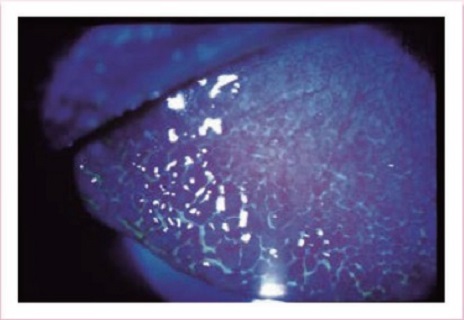

眼瞼けいれん

日本眼科学会画像 引用

まぶたを閉じる筋肉(眼輪筋)の持続的な収縮によって、意に反して目を閉じてしまう(閉じていると楽な)、40歳以上の女性に多い病気です。瞬きの増加、眩しさといった主症状に加え、目の乾燥、ショボショボ感、まぶたのぴくぴくとした痙攣などが見られます。当院では、神経眼科にて眼瞼けいれんの専門的な治療を行っています。